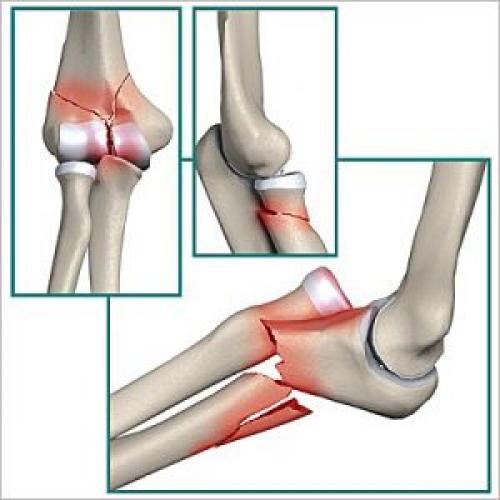

Травмы локтевого сустава в дзюдо. Острые травмы локтя

Переломы:

Костей в суставе три и основных видов переломов тоже три: нижней части плечевой кости, головки лучевой кости и отростка (олекранон) локтевой кости:

Механизм возникновения всех этих переломов одинаков: либо неудачное падение (часто на вытянутую руку), либо удар по локтю, либо(в борьбе)-переразгибание локтя против анатомического сгиба.

Симптомы тоже очень похожи:очевидная деформация над суставом,чрезвычайная боль, усиливающаяся при попытке движения в локте, опухоль, гематома.

Первая помощь будет заключаться в ужу набившей оскомину методике ПЛДП (покой-лед-давление-приподнятое положение), которую я не устаю пропагандировать как очень простую и высокоэффективную. По необходимости, как всегда, принимаются обезболивающие. После наложения фиксирующей повязки (иммобилизация) пострадавший немедленно доставляется в травмопункт, где ему сделают рентгенграфию (в дальнейшем,возможно и КТ или МРТ). Дальнешее лечение будет в руках профессионалов…

Здесь необходимо сделать небольшое лирическое отступление. Помимо того,что локтевой сустав имеет сложное строение сам по себе,через него проходят очень важные сосуды и нервы,которые именно здесь выходят на поверхность и могут быть легко повреждены с самыми печальными последствиямивплоть до утраты функций руки на всю жизнь.

Отсюда два важных вывода:

1)Травмированный локоть обязательно нужно показать врачу травматологу-ортопеду чтобы не пропустить осложнения. Например, в случае перелома может понадобиться сопоставление и хирургическое скрепление отломков костей(остеосинтез).

2)Сейчас врачи отходят от использования традиционных гипсовых лонгет для длительной иммобилизации,заменяя их съемными шинами, позволяющими проводить раннюю активизацию сустава во избежание развития тугоподвижности.

Например, даже в случае перелома со смещением отломков, потребовавшего хирургической операции такая шина накладывается обычно лишь на 3 недели (максимум 6-8), а разработка подвижности начинается уже после первой недели (шина естественно потом снова одевается).